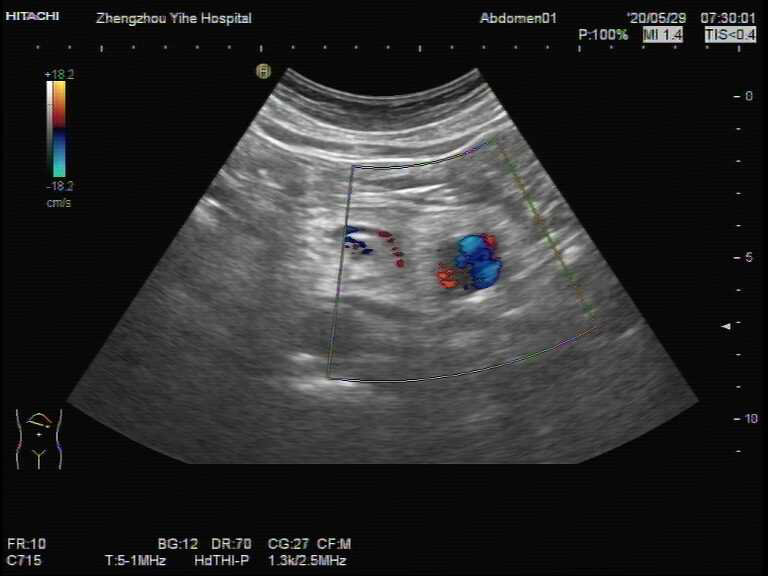

一位五十多岁男性进入诊室,这是他们单位每年例行常规来体检,彩超医生仔细认真的检查腹部各个脏器,当查至胰腺时,似乎未见明显的异常,但再仔细观察后发现胰腺的尾部后下方好像有模糊的包块。会不会是胰腺的肿块呢?彩超医生调节机器,包块逐渐清晰,是一个大小约29x23mm囊性回声。是囊肿吗?又是一个疑问!接下来医生对这个包块加个彩色多普勒,里面迅速充满了血流,哦!原来是个血管!是动脉还是静脉呢?利用频谱多普勒鉴别一下,答案马上出来:是动脉血流!(图1、2)

图2